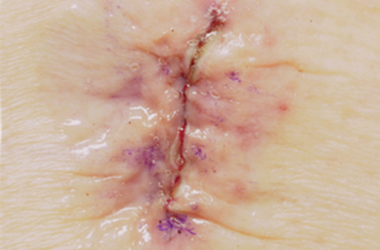

Wound complications

Most surgical wounds will heal without any problems. It is possible that your wound may become infected after surgery. A surgical wound infection can develop at any point (up to several months after).

Signs that you may have a wound infection include:

The wound becoming more painful

Redness in and around the wound

Leaking of blood or pus from the wound

Swelling of the wound – an abscess (a collection of pus) may have formed

An unpleasant smell coming from the wound

Having a raised temperature

Don’t worry if there’s a bit of oozing from your wound within the first few hours. Other complications can include the wound gaping open, or some of the stitches or staples coming away. However, if you have any of these symptoms or are worried about how your wound looks, please seek advice from your healthcare professional, unless you have been told to contact the hospital.